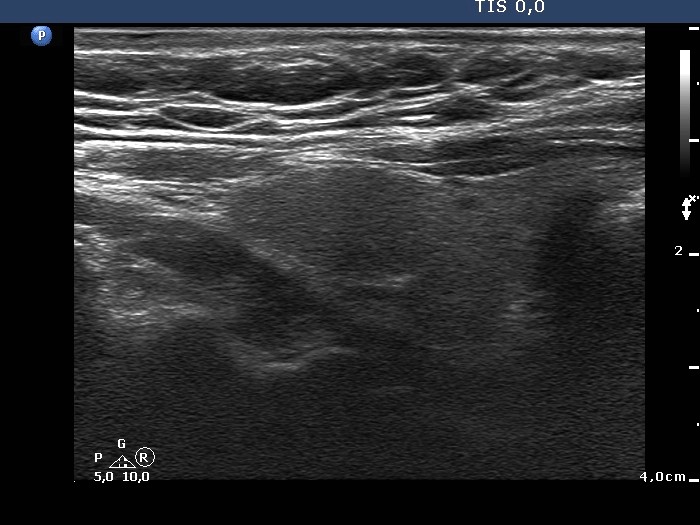

Benign nodular hyperplasia - Case 50. (ultrasonographic picture 2)

Right lobe, longitudinal scan.